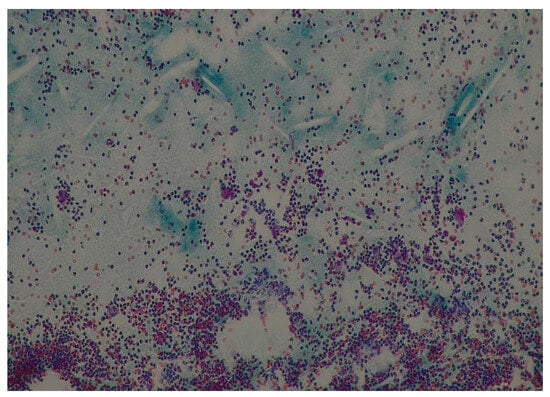

2.2.1. Case 1

2.2.2. Case 2

2.2.3. Case 3